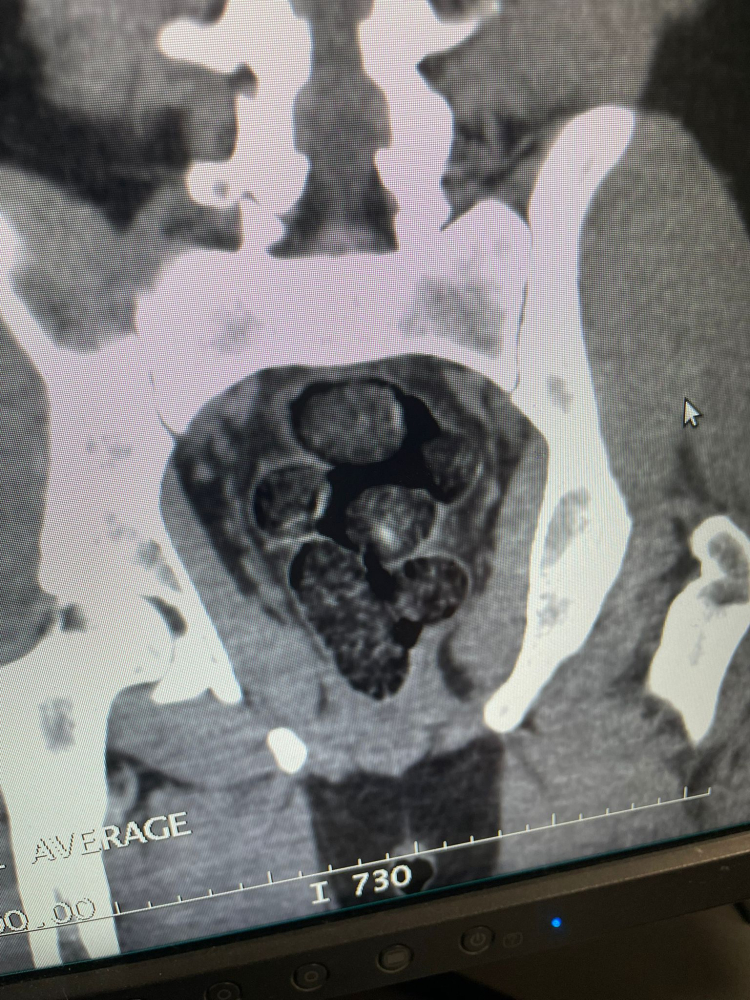

Hastaneye götürülüp, tomografisi çekilen şüphelinin midesinden poşete sarılmış, 10 adet olmak üzere toplamda 191,18 gram metamfetamin ele geçirildi.